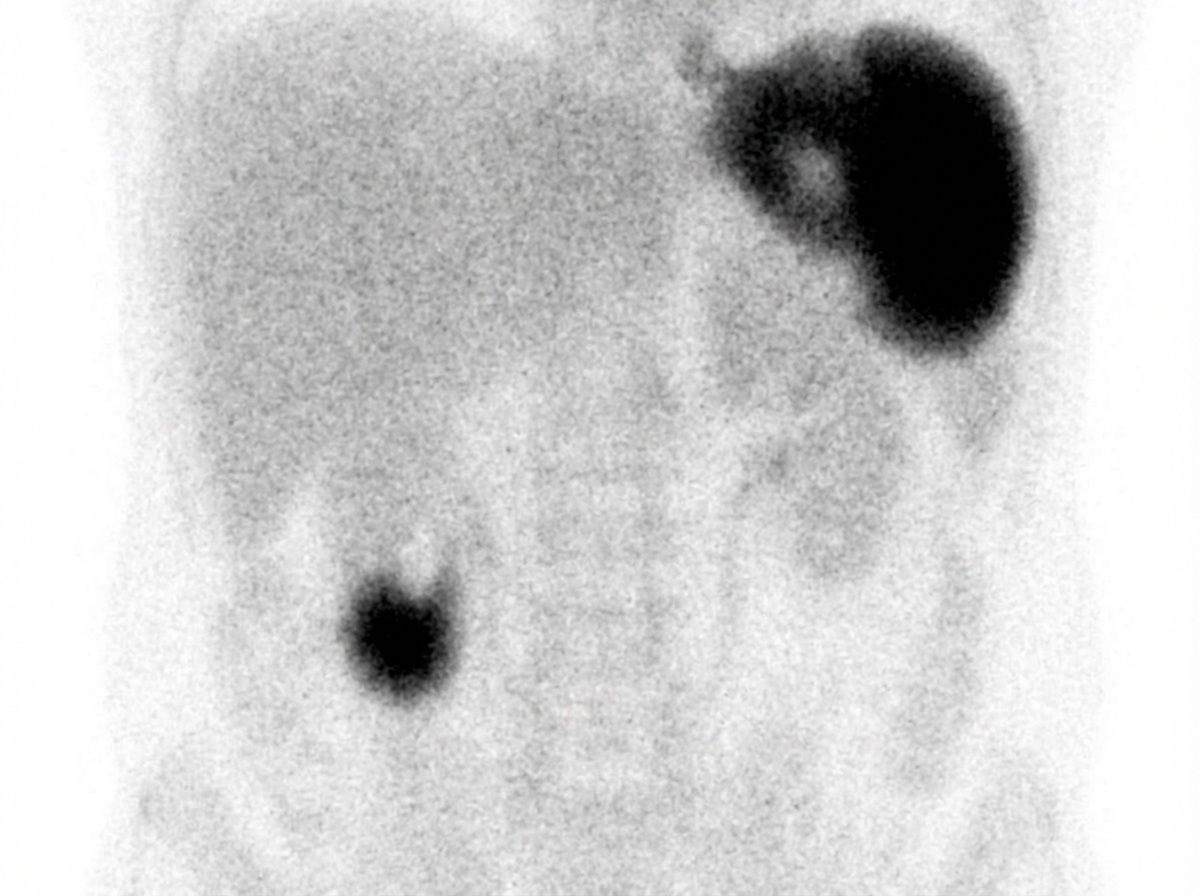

Explanation: ***Tolazoline*** - **Tolazoline** is an **alpha-adrenergic blocker** used as a pharmacological adjunct in **Meckel's diverticulum scintigraphy** to inhibit the release of **Tc-99m pertechnetate** from ectopic gastric mucosa. - By blocking gastric acid secretion, it enhances **visualization** of the Meckel's diverticulum by allowing greater accumulation of the radiotracer in the ectopic gastric tissue. *Clonidine* - **Clonidine** is an **alpha-2 agonist** used primarily for **hypertension** and **ADHD**, not for nuclear medicine imaging studies. - It has no role in **Meckel's diverticulum scintigraphy** and would not enhance visualization of ectopic gastric mucosa. *Bismuth* - **Bismuth** compounds are used for **H. pylori eradication** and as **antidiarrheal agents**, not in nuclear imaging procedures. - It would interfere with **Tc-99m pertechnetate** uptake rather than enhance visualization in Meckel's scan. *Oxymetazoline* - **Oxymetazoline** is an **alpha-1 agonist** used as a **nasal decongestant** with vasoconstrictor properties. - It has no application in **nuclear medicine** and would not be beneficial for enhancing Meckel's diverticulum visualization.